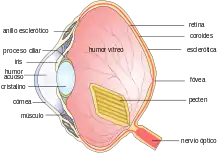

Dibujo esquemático del ojo humano. | ||

La estructura y el funcionamiento del ojo es muy similar en la mayoría de los vertebrados. El globo ocular es básicamente una esfera llena de un líquido transparente, llamado humor acuoso, que está compuesto por un 99 por ciento de agua. La pared está formada por 3 capas: la más interna o retina, la intermedia o coroides, y la más externa, que se llama esclerótica.

Posee una lente llamada cristalino, que es ajustable según la distancia; un diafragma, que se llama pupila (cuyo diámetro está regulado por el iris), y un tejido sensible a la luz, que es la retina.

Con la excepción de los peces, anfibios y ofidios, el enfoque se consigue gracias al cambio de forma del cristalino mediante un músculo llamado músculo ciliar.

La luz penetra a través de la pupila, atraviesa el cristalino y se proyecta sobre la retina, donde se transforma, gracias a unas células llamadas fotorreceptoras, en impulsos nerviosos, que son trasladados, a través del nervio óptico, hasta el cerebro.

Aves

En el ojo de las aves existen diferentes adaptaciones, el tamaño del órgano es proporcionalmente más grande respecto al cuerpo que en los mamíferos, y la acomodación tiene lugar mediante un doble mecanismo que permite cambiar la curvatura de la córnea y del cristalino.

La retina es muy rica en células fotorreceptoras, lo que hace suponer que la visión es excelente, y en algunas especies existen dos fóveas, una central y otra más periférica, como ocurre en los halcones, en las águilas y en los vencejos.[13]

Una estructura característica de los ojos de las aves que no existe en los mamíferos es el pecten, un tejido que contiene una vasta red de vasos sanguíneos con apariencia de peine que, partiendo de una de las capas que forman la pared del ojo, la coroides, penetra en el humor vítreo. No se sabe qué función precisa desempeña, aunque se cree que proporciona oxígeno y nutrientes a la retina.[8]